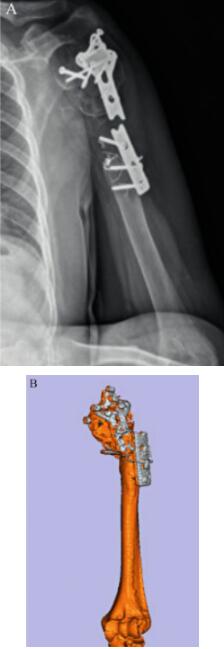

患者,男性,左侧半肩关节置换术后5年,因“疼痛伴活动受限”收入我院(图5)。

2、病例分析:

X线及CT重建可见患者肱骨有较大范围的缺损,且由于之前定制的假体长短及肱骨头假体的直径匹配问题,造成关节盂的破坏,该患者只能根据当前状况重新设计全肩关节。当前反式肩关节效果较好,且能满足该患者关节方面的需求,再利用3D打印技术对缺损部位进行重建,纠正不合适的长度和角度,可重新建立患者肩关节的解剖和功能。综上考虑,将反肩关节的肱骨组件以20°~40°放置能够提供更大的外旋角度。肱骨组件扭转角按照30°放置。在此基础上取得患者的知情同意后,对该患者的肩关节进行个体化的设计和制造(图6)。

图5 患者术前X线图像A.患者第一次常规定制假体植入术前;B.患者常规定制假体失败;C.常规定制假体取出术后。